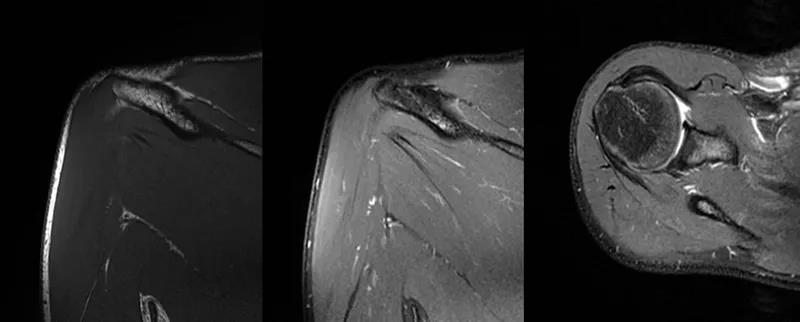

2、MRI检查MRI目前是诊断肩袖疾病中最常用的检查,可以直观的观察肩袖肌腱。

图24 a.肩袖全层撕裂;b.正常MRI

图25 巨大肩袖损伤(冈上肌)